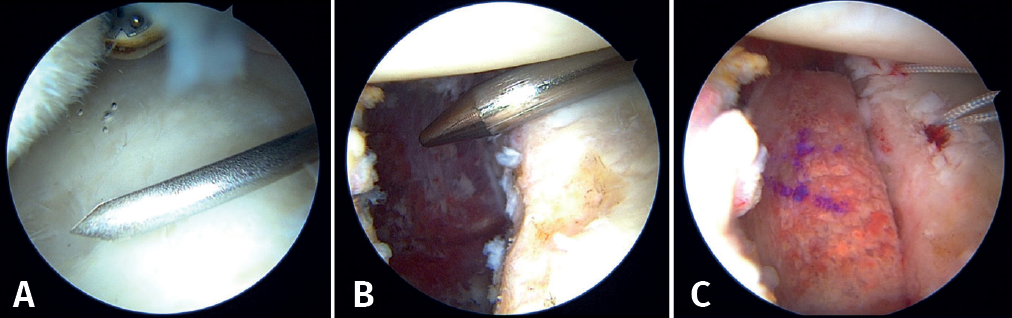

First, the glenoid is debrided with the aid of a shaver-type motor, and free bodies and bony debris are removed. The labrum and capsule are detached together from the glenoid margin, creating a wide recess to accommodate the graft, and the surface is prepared by creating bleeding edges with a burr. Then, using a posteroinferior auxiliary portal established under direct vision (Figure 3A), remplissage is started with debridement of the Hill-Sachs lesion and the placement of two bone implants - in this case HealicoilRegenesorb® (Smith & Nephew Inc., Andover, MA, USA) 4.5 mm double suture Ultrabraid® N.2 (Smith & Nephew Inc., Andover, MA, USA ) (Figures 3B and 3C). The 8 extremities are retrieved, passing them through the capsule approximately 1 cm apart and using a Sling-Shot® device (Stryker) (Figures 3D, 3E and 3F). The extremities are left untied in the posterior portal.